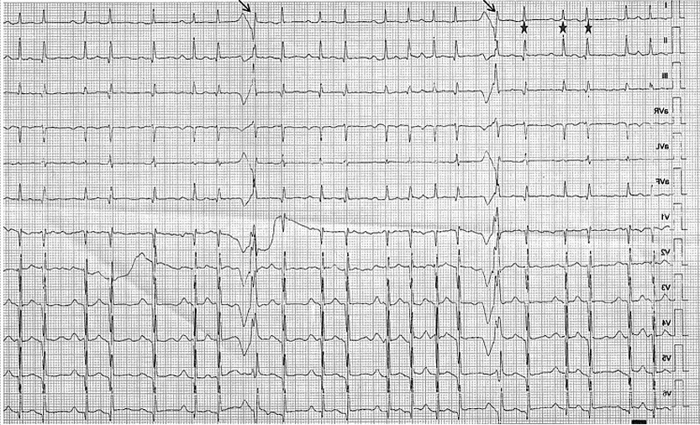

Observe a imagem a seguir.

Em relação a esse ECG, nota-se que esse paciente se apresenta em ritmo de fibrilação atrial, e que os batimentos marcados pela seta se apresentam com QRS alargado, que ocorre devido à variação do comprimento do intervalo RR, marcados pelas estrelas, com ciclo longo seguido por um ciclo curto, com o próximo complexo QRS conduzido com aberrância pela variação do período refratário do feixe de His. Este fenômeno é denominado de